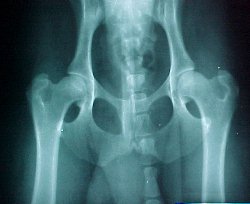

Figure 1 shows the proper positioning.

a. Inclusion of the pelvis, femurs and stifles

b. Symmetrical position

1. Equal width of the wings of the ilia.

2. Equal size of the obturator foramina

3. Parallel femurs with the patella

positioned on the midline of the

distal femurs.

OFA will evaluate the following factors:

a. Joint space

b. Amount of femoral head within the

acetabulum. (a minimum 1/2)

c. Shape (roundness and smoothness) of femoral head.

The fovea capitus is a normal flattened area on the

femoral head.  This is where the femoral ligament attaches.

d. The femoral neck, which should be smooth and free of dysplastic changes.

e. The angle of the femoral neck which should be approximately

130 degrees.